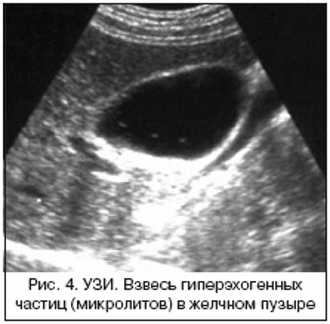

Взвесь, скапливающаяся в полости желчного, представлена в виде мельчайших песчинок. Состав взвеси сложный — в ней присутствуют кристаллизованные частицы липидов и холестерина, белок и соли кальция. По мере увеличения количества взвеси частицы слипаются, образуя более объемные структуры — конкременты. Образование твердой взвеси из застоявшейся в полости пузыря желчи называют сладж-синдромом.

Взвесь, скопившаяся в полости желчного, может иметь разный состав:

- микролитиаз, или мелкодисперсная взвесь — мелкий осадок, состоящий из солей калия и кальция, белковых частиц; микролитиаз легко выявляют во время УЗИ — осадок перемещается внутри желчного при смене пациентом положения тела;

- сладж — патологические образования в полости пузыря, представленные в виде замазкообразных сгустков желчного секрета;

- сладжированная желчь — комбинация из мелкодисперсного осадка и желчных сгустков; образование сладжированной желчи считают ранней стадией желчнокаменной болезни.

Как осадок выглядит на УЗИ?

Диагностирование патологии